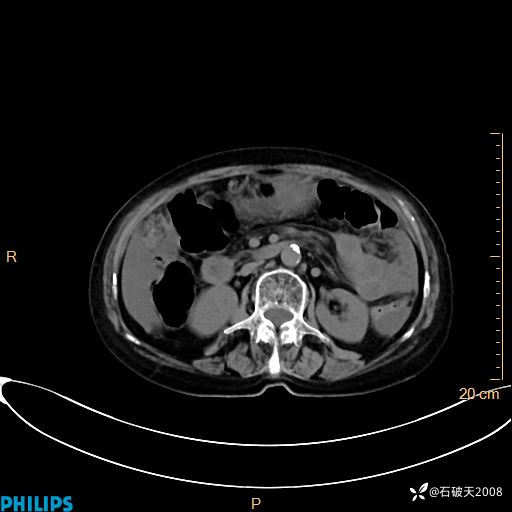

MIP